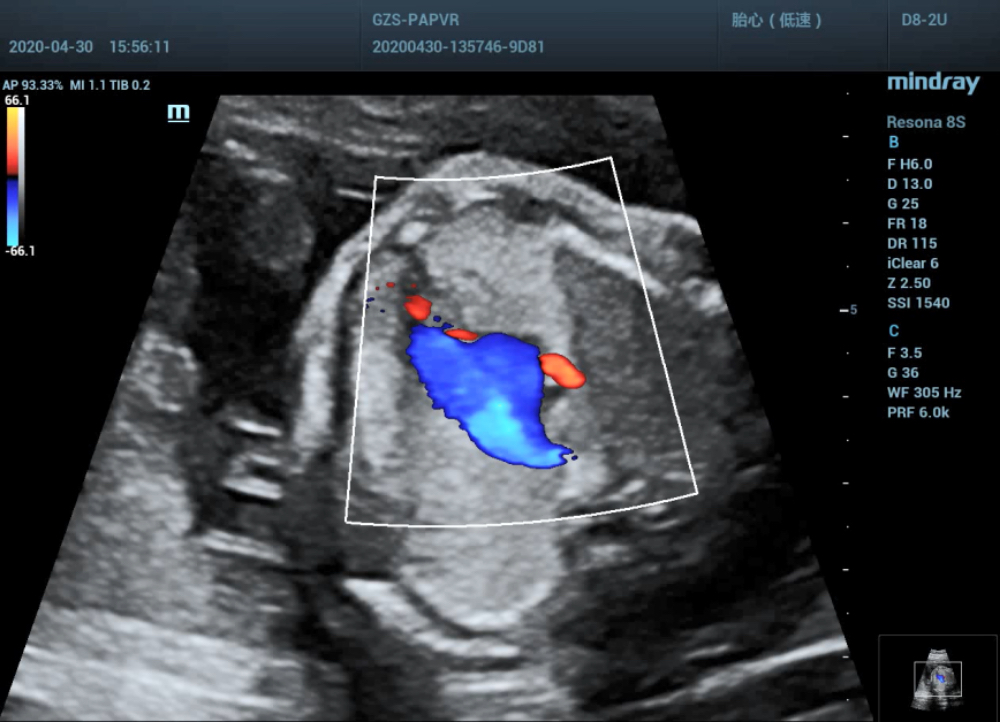

Three-vessel and trachea view

•  The consistent connection between ventricle and a great artery .Normal original and size of aorta and pulmonary artery, blood flow unobstructed. Normal Semilunar valve shape and function.

•  Normal course and diameter of ductus arteriosus and aortic arch, and unobstructed blood flow.